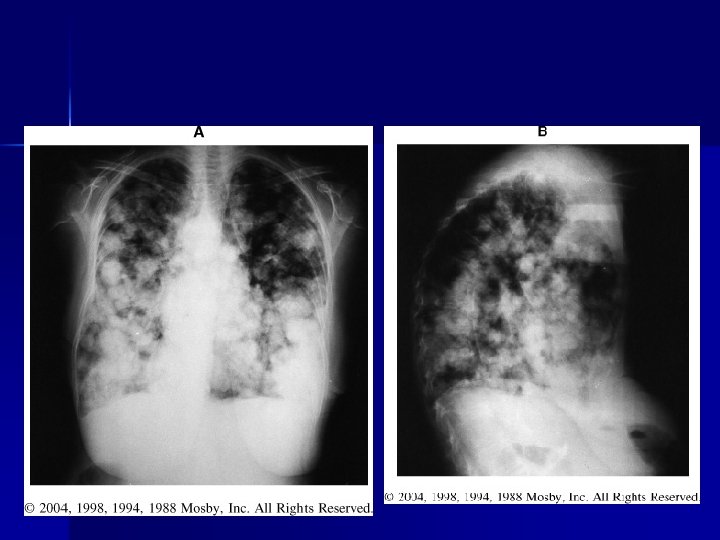

PATHOLOGY NOT ARTIFACT

Name & cause of this?

Evaluating Images What do you think?

n n n Does this show good detail? Is all of the anatomy present? How is the density / contrast?